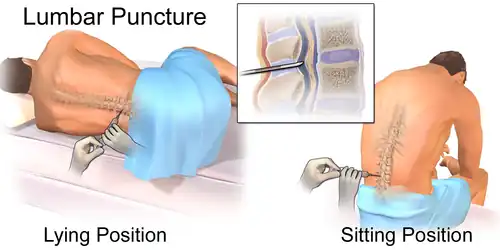

The most widely-used prophylactic drug is methotrexate (MTX), which is normally administered by one of two methods: intravenous injection (IV HD-MTX) and intrathecal injection (IT-MTX).[1][4] Intravenous injection requires a direct injection of high-dose MTX into a patient’s vein;[4] Intrathecal injection, i.e. injection of the drug into the intrathecal space holding cerebrospinal fluid (CSF), is either administered via the Ommaya reservoir, an implanted container passing fluid into the brain, or by lumbar puncture.[1]

The other solution is intrathecal injection of MTX. One method is by surgically implanting under the scalp an Ommaya reservoir, to be attached to a ventricular catheter leading into the ipsilateral anterior horn. The implant provides long-term access to the cerebrospinal fluid and is used for administration of antimicrobials, antifungals, antineoplastic and analgesic medications.[11] Alternatively, MTX may be injected into the intrathecal space via lumbar puncture. After sterilization and local anesthetic, or general anesthesia in paediatric practice, a needle is used to inject MTX between the L3 and L4 or L4 and L5 vertebrae to avoid damage to the conus medullaris.[12]